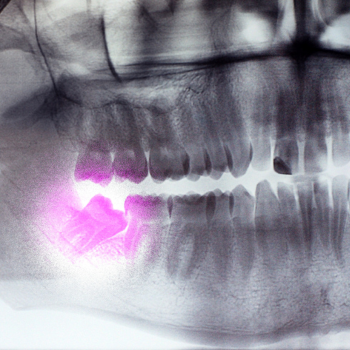

שיני הבינה, או הטוחנות השלישיות, הן לעיתים קרובות מקור לאי נוחות, זיהומים ואפילו נזק מבני לשיניים סמוכות. בעוד שבמקרים מסוימים ניתן לחיות איתן, לעיתים קרובות הן דורשות עקירה כירורגית. ההחלטה על הצורך בטיפול זה מתחילה בצילום אבחנתי מדויק. צילום פנורמי ו/או צילום CT דנטלי הם כלי האבחון הבלעדיים להערכת המיקום, הזווית והקשר של שן הבינה למבנים עצביים קריטיים בלסת (כגון העצב המנדיבולרי), דבר המכריע את דרגת המורכבות של העקירה כירורגית.

במרפאה אנו נתקלים במקרים רבים המדגישים את חשיבות הניסיון המקצועי. לדוגמה, טופל מטופל בשנות העשרים לחייו אשר הופנה אלינו עם שן בינה כלואה תחתונה, ששכבה בצורה אופקית לחלוטין, וראשה נח באופן ישיר על תעלת העצב המנדיבולרי (עצב הלסת התחתונה). עקירה שגרתית במקרה כזה הייתה כרוכה בסיכון גבוה מאוד לפגיעה עצבית קבועה.

- תכנון מדויק- בוצע צילום CT תלת-ממדי (CBCT) שהבהיר את המרחק המדויק בין השורש לעצב.